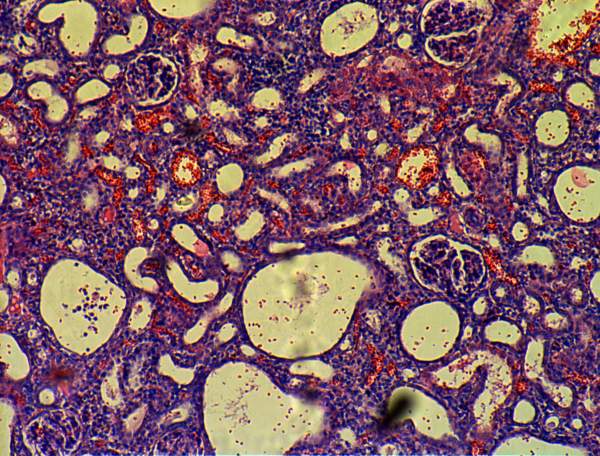

间质性肾炎切片观察